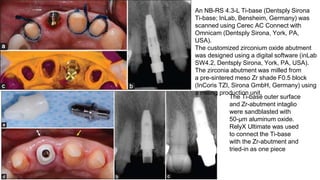

An NB-RS 4.3-L Ti-base (Dentsply Sirona

Ti-base; InLab, Bensheim, Germany) was

scanned using Cerec AC Connect with

Omnicam (Dentsply Sirona, York, PA,

USA).

The customized zirconium oxide abutment

was designed using a digital software (inLab

SW4.2, Dentsply Sirona, York, PA, USA).

The zirconia abutment was milled from

a pre-sintered meso Zr shade F0.5 block

(InCoris TZI, Sirona GmbH, Germany) using

a milling production unit.

The Ti-base outer surface

and Zr-abutment intaglio

were sandblasted with

50-μm aluminum oxide.

RelyX Ultimate was used

to connect the Ti-base

with the Zr-abutment and

tried-in as one piece